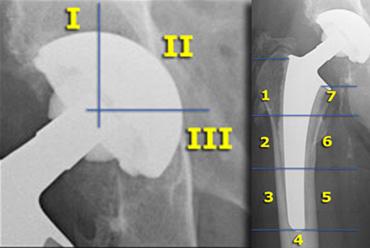

Tại ổ cối, có ba vùng được đánh dấu từ I đến III.

Việc nhìn thấy đường thấu quang tại vùng I là khá phổ biến, nhưng không nên thấy ở vùng II và III.

Tương tự, tại xương đùi có các vùng từ 1 đến 7. Vùng thấu quang rất thường gặp ở vùng 1, đôi khi ở vùng 7, nhưng không nên xuất hiện ở vùng dưới mấu chuyển lớn từ vùng 2 đến 6.